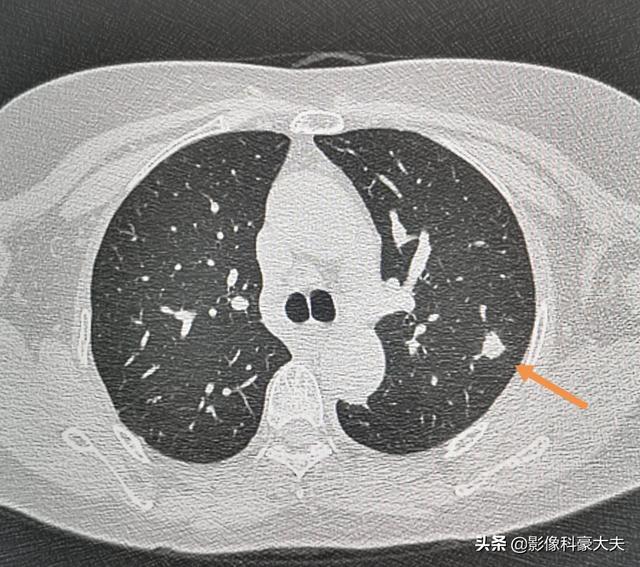

炎症性結節は成長が早く、1ヵ月も経たないうちに1センチ以上になることもあるが、適切な抗炎症治療を行えばすぐに吸収される。

この患者は高齢者で、健康診断で肺結節が見つかり、2ヵ月後に吸収され、何の治療も行わず、ただ安静と適切な運動に注意し、病原性の低い感染症と考えられた。